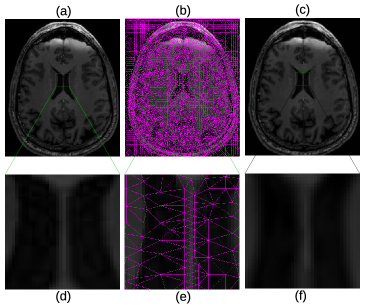

In Fig. 4, more details of the Lena experiment are shown. (a) is the original Lena image, the same as Fig. 3 (a). (b) is the mesh generated by the method outlined in section 2.1. (c) is the recovered image, which is the same as Fig. 3 (e). To visually see the generated mesh and compare the difference between the original and restored images, Fig. 4 (d)–(f) are the zoomed-in views of (a)–(c), respectively. As the results show, the mesh quality is high enough for subsequent numerical analysis and the the recovered image is very close to the original one. As a matter of fact, the restored image looks smoother due to the smooth radial basis functions used, and the sharp edge features are well preserved. Fig. 5 shows the original brain MRI, its generated mesh, and the result of ARBF interpolation using intensities on triangle centers with the MQ basis function. The zoomed-in views show the quality of mesh and restoration as well. Fig. 6 shows another MRI experiment of breast. Fig. 7 shows a CT-scanning experiment. From all these examples, one can see the effectiveness of the proposed approaches for image mesh generation and feature-preserving restoration.

Figure 5: Details of brain MRI. (a) Original brain MRI. (b) Generated mesh of (a). (c) Result of triangle-based ARBF interpolation using MQ basis. (d)–(f) are zoomed-in views of (a)–(c), respectively.

Refer to caption

Brain 285×341285341285\times 341 6% 15.7058 0.5 1.71